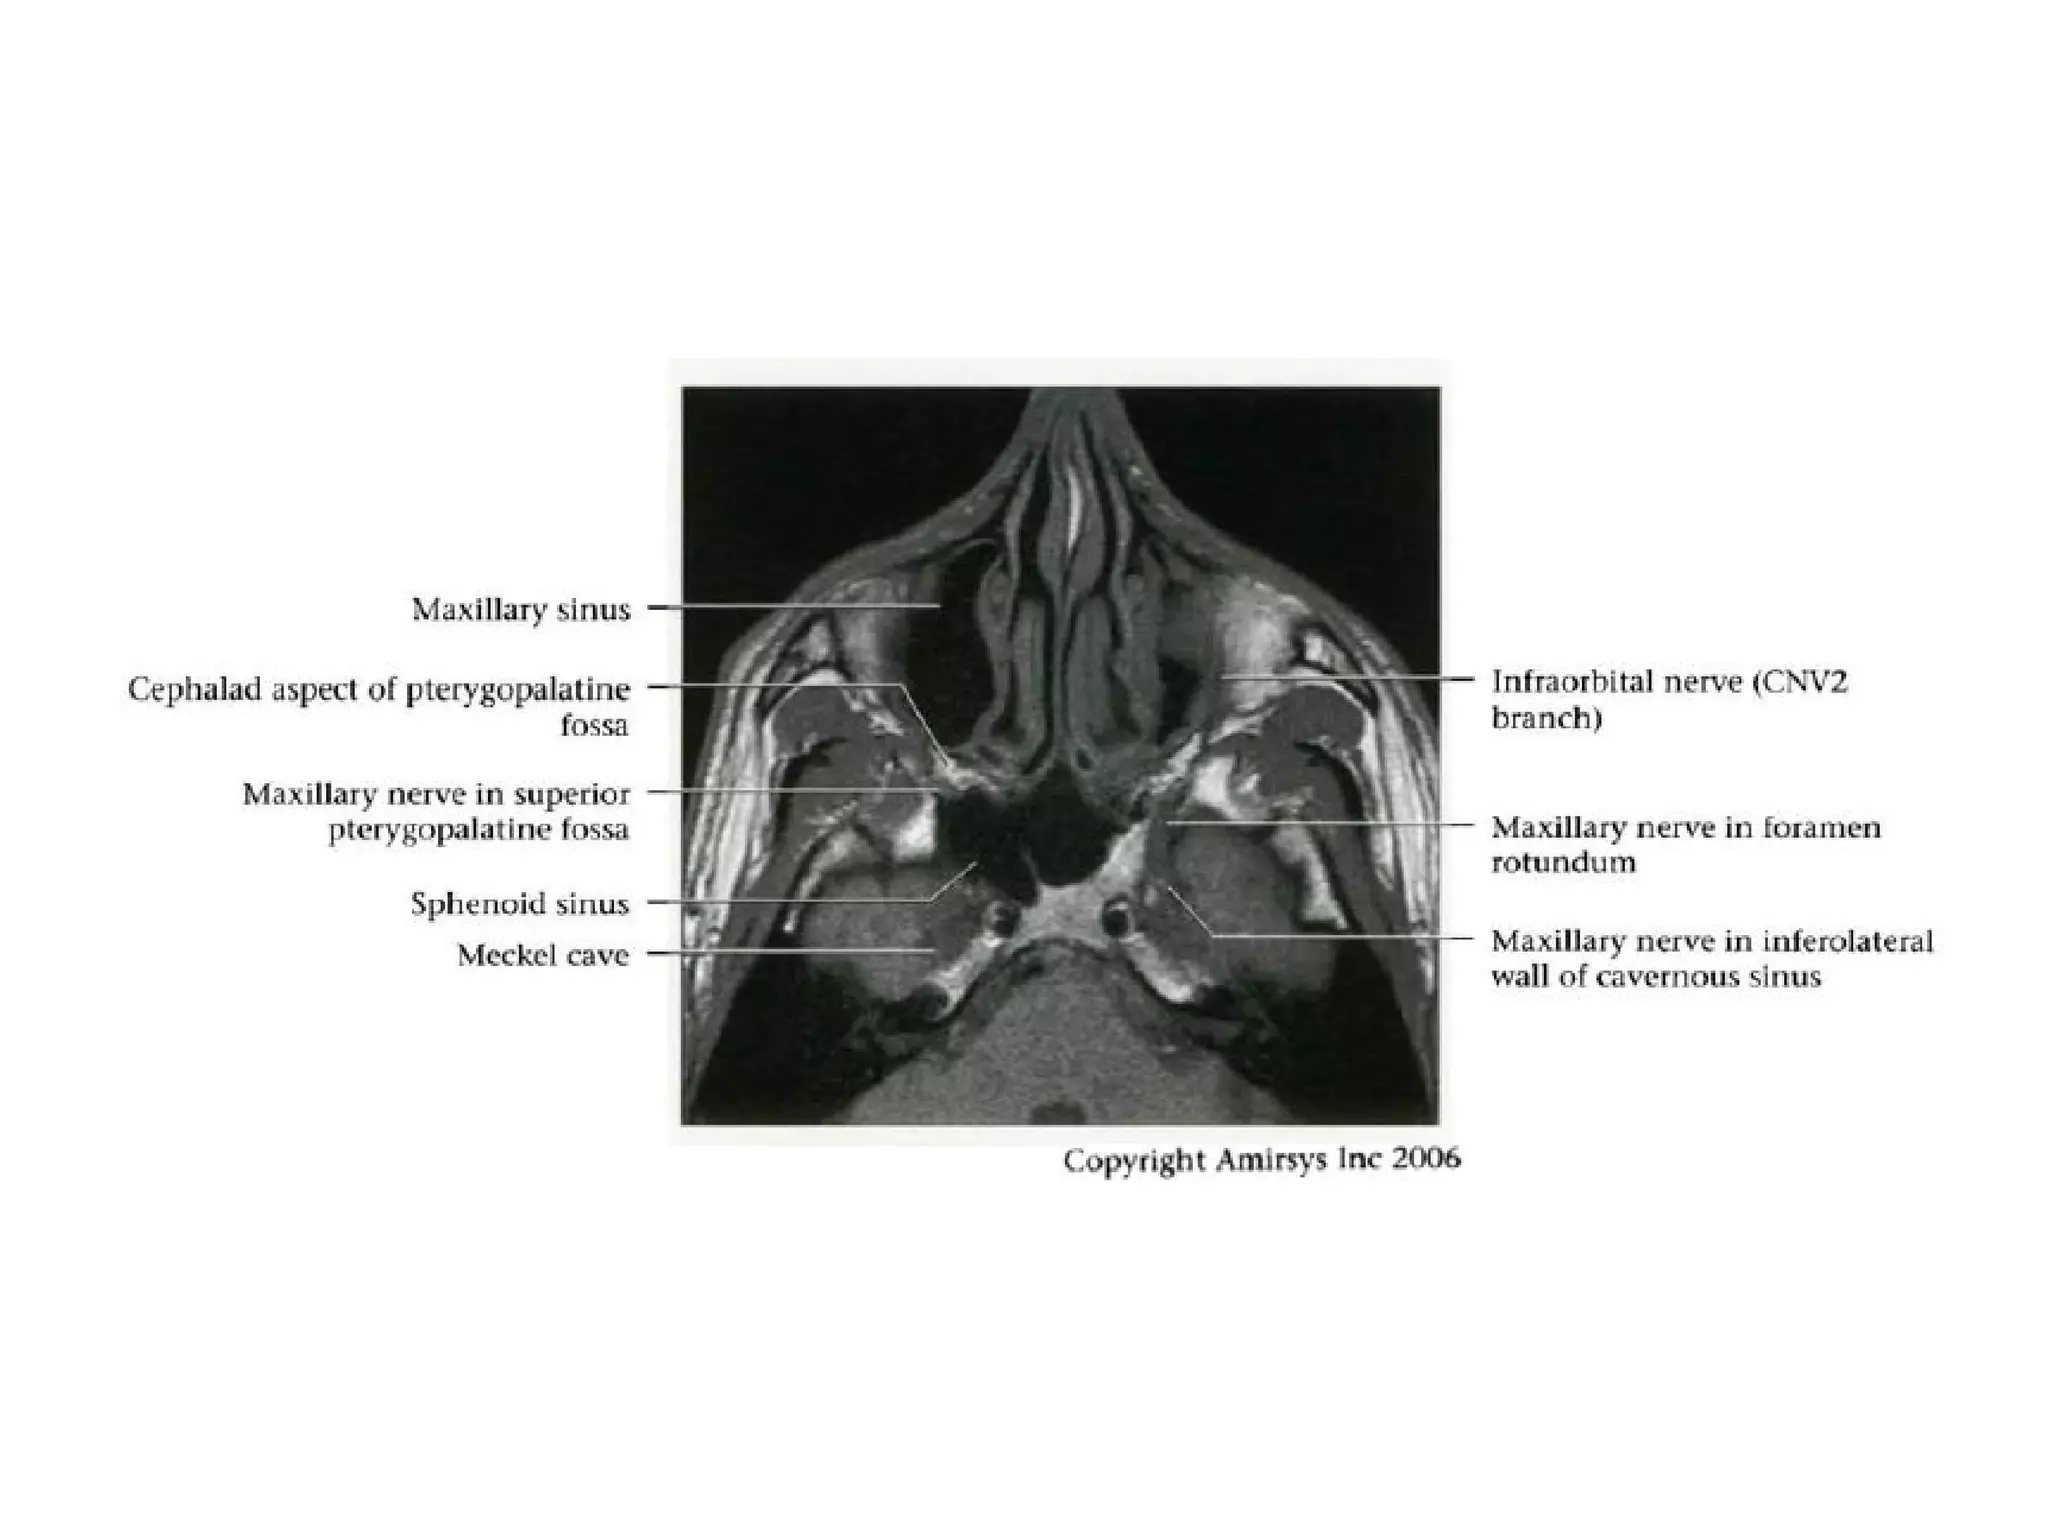

Divisions (Post-Ganglionic) of CNS

Maxillary nerve (CNV2)

• Courses in cavernous sinus lateral wall

below CNV 1

• Exits skull through foramen rotundum

• Traverses roof of pterygopalatine fossa

• Continues as infraorbital nerve in floor of

orbit

• Exits orbit through infraorbital foramen

- Sensory to cheek and upper teeth